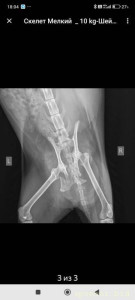

Добрый день, меня зовут Алексей, мы нашли на работе кошку у которой сломан таз. Мы отвезли ее на рентген там нам сказали что кошке требуется операция остеозинтез. Кошка плохо ходит в туалет. Есть и пьет вроде хорошо. Сейчас кошка в стационаре под наблюдением. Кошке срочно нужна операция, но для начала надо сдать все анализы и пройти обследования. Все необходимые документы я приложу если надо могу прислать видео кошки на WhatsApp. Кошка пытается ходить и вставать но ей очень тяжело. На операцию надо 30-50 тысяч рублей + реабилитация. Мы собрали 20 тысяч, но много денег ушло на осмотры, рентген, лекарства и стационар. Не знаю где просить помощи. Писал в фонды, но там тоже не густо ( свои хватает животных ). Будем признательны любой помощи. Заранее спасибо!!! Более подробно в WhatsApp.